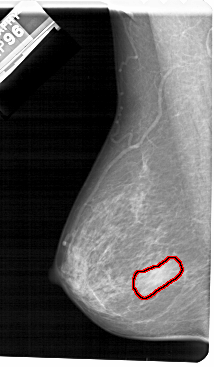

A_1483_1.LEFT_CC

FILE: A_1483_1.LEFT_CC.OVERLAY

TOTAL_ABNORMALITIES 1

ABNORMALITY 1

LESION_TYPE MASS SHAPE IRREGULAR MARGINS ILL_DEFINED

ASSESSMENT 4

SUBTLETY 5

PATHOLOGY BENIGN

TOTAL_OUTLINES 1

BOUNDARY